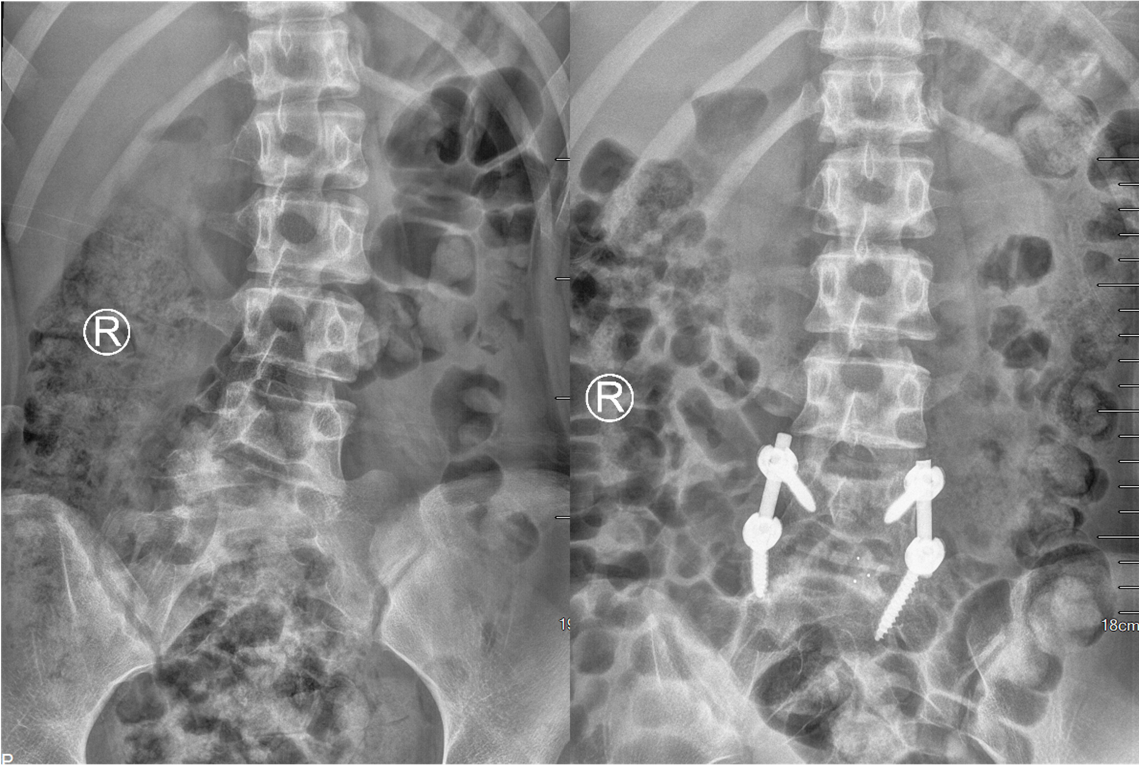

入院进一步完善各项检查后,姜为民主任再一次对小王的影像资料进行了全面的研究,同时与团队成员商讨制定详细的手术方案。计划首先经后路切除L5半椎体,然后行椎间盘摘除凹侧椎间隙撑开矫形,再置入融合器行椎间融合,最后行短节段椎弓根内固定,以尽可能小的代价取得较为理想的效果。手术当日,姜主任熟练的通过截骨、置钉、撑开矫形、植骨融合等操作,顺利完成了手术。术后,患者小王恢复良好,术后影像检查显示半椎体已完全切除,矫形效果满意,手术非常成功。